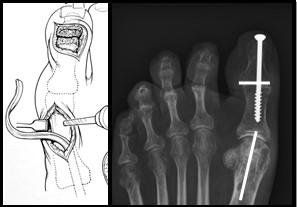

Figuur 5: Op het linker plaatje is de grote teen zichtbaar. Er worden 2 littekens gemaakt. De pees wordt losgehaald bij het eindkootje en door het middenvoetsbeentje gevlochten door een boorgat. Op de rechter foto is de schroef zichtbaar die beide kootjes aan elkaar verbindt. Deze wordt vanuit het puntje van de teen geboord middels een (klein) 3e litteken. De witte streepjes geven de locatie van de andere 2 littekens aan.

Figuur 4: Het bovenste linker plaatje is een schematische weergave van de “osteotomie”. Het driehoekje bij de pijl wijst naar de wig die uitgezaagd wordt. Het plaatje eronder laat de situatie zien na verwijderen van het wigje. Het middelste plaatje laat een voetfoto van een patiënt zien voor de operatie, de witte streep is de plaats van het litteken. het meest rechtse plaatje is na de operatie. Bij de pijl zie je de schroef en het ijzerdraadje om de botdelen op de juiste positie te houden.